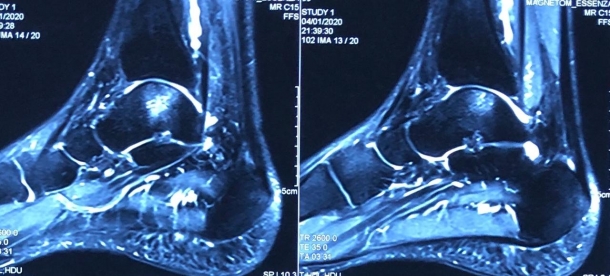

He was thoroughly examined with an MRI scan of ankle, which showed a defect in cartilage of around 18 mm x 20 mm over the left talar dome in the weight bearing axis. This was the real reason for his pain. He couldn't remember the exact reason for the injury too. Later he doubted about the ankle injury which he met with long ago.